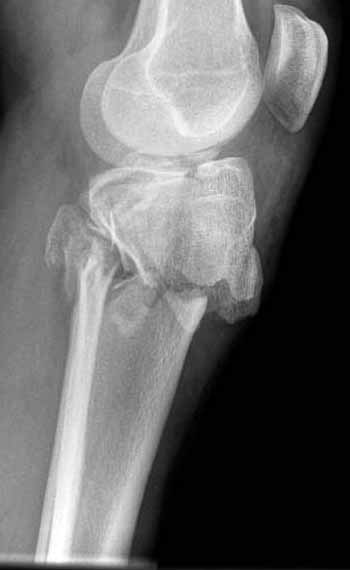

Двухколоннный перелом тибиал плато с вовлечением проксимального диафиза. Внутрисуставной компонент без смещения, и такой перелом можно лечить любым из описанных методов, о которых говорят наши коллеги.

В приложении этапы фиксации Both Column Fx и пластиной Synthes для плеча при переломе медиального мыщелка.